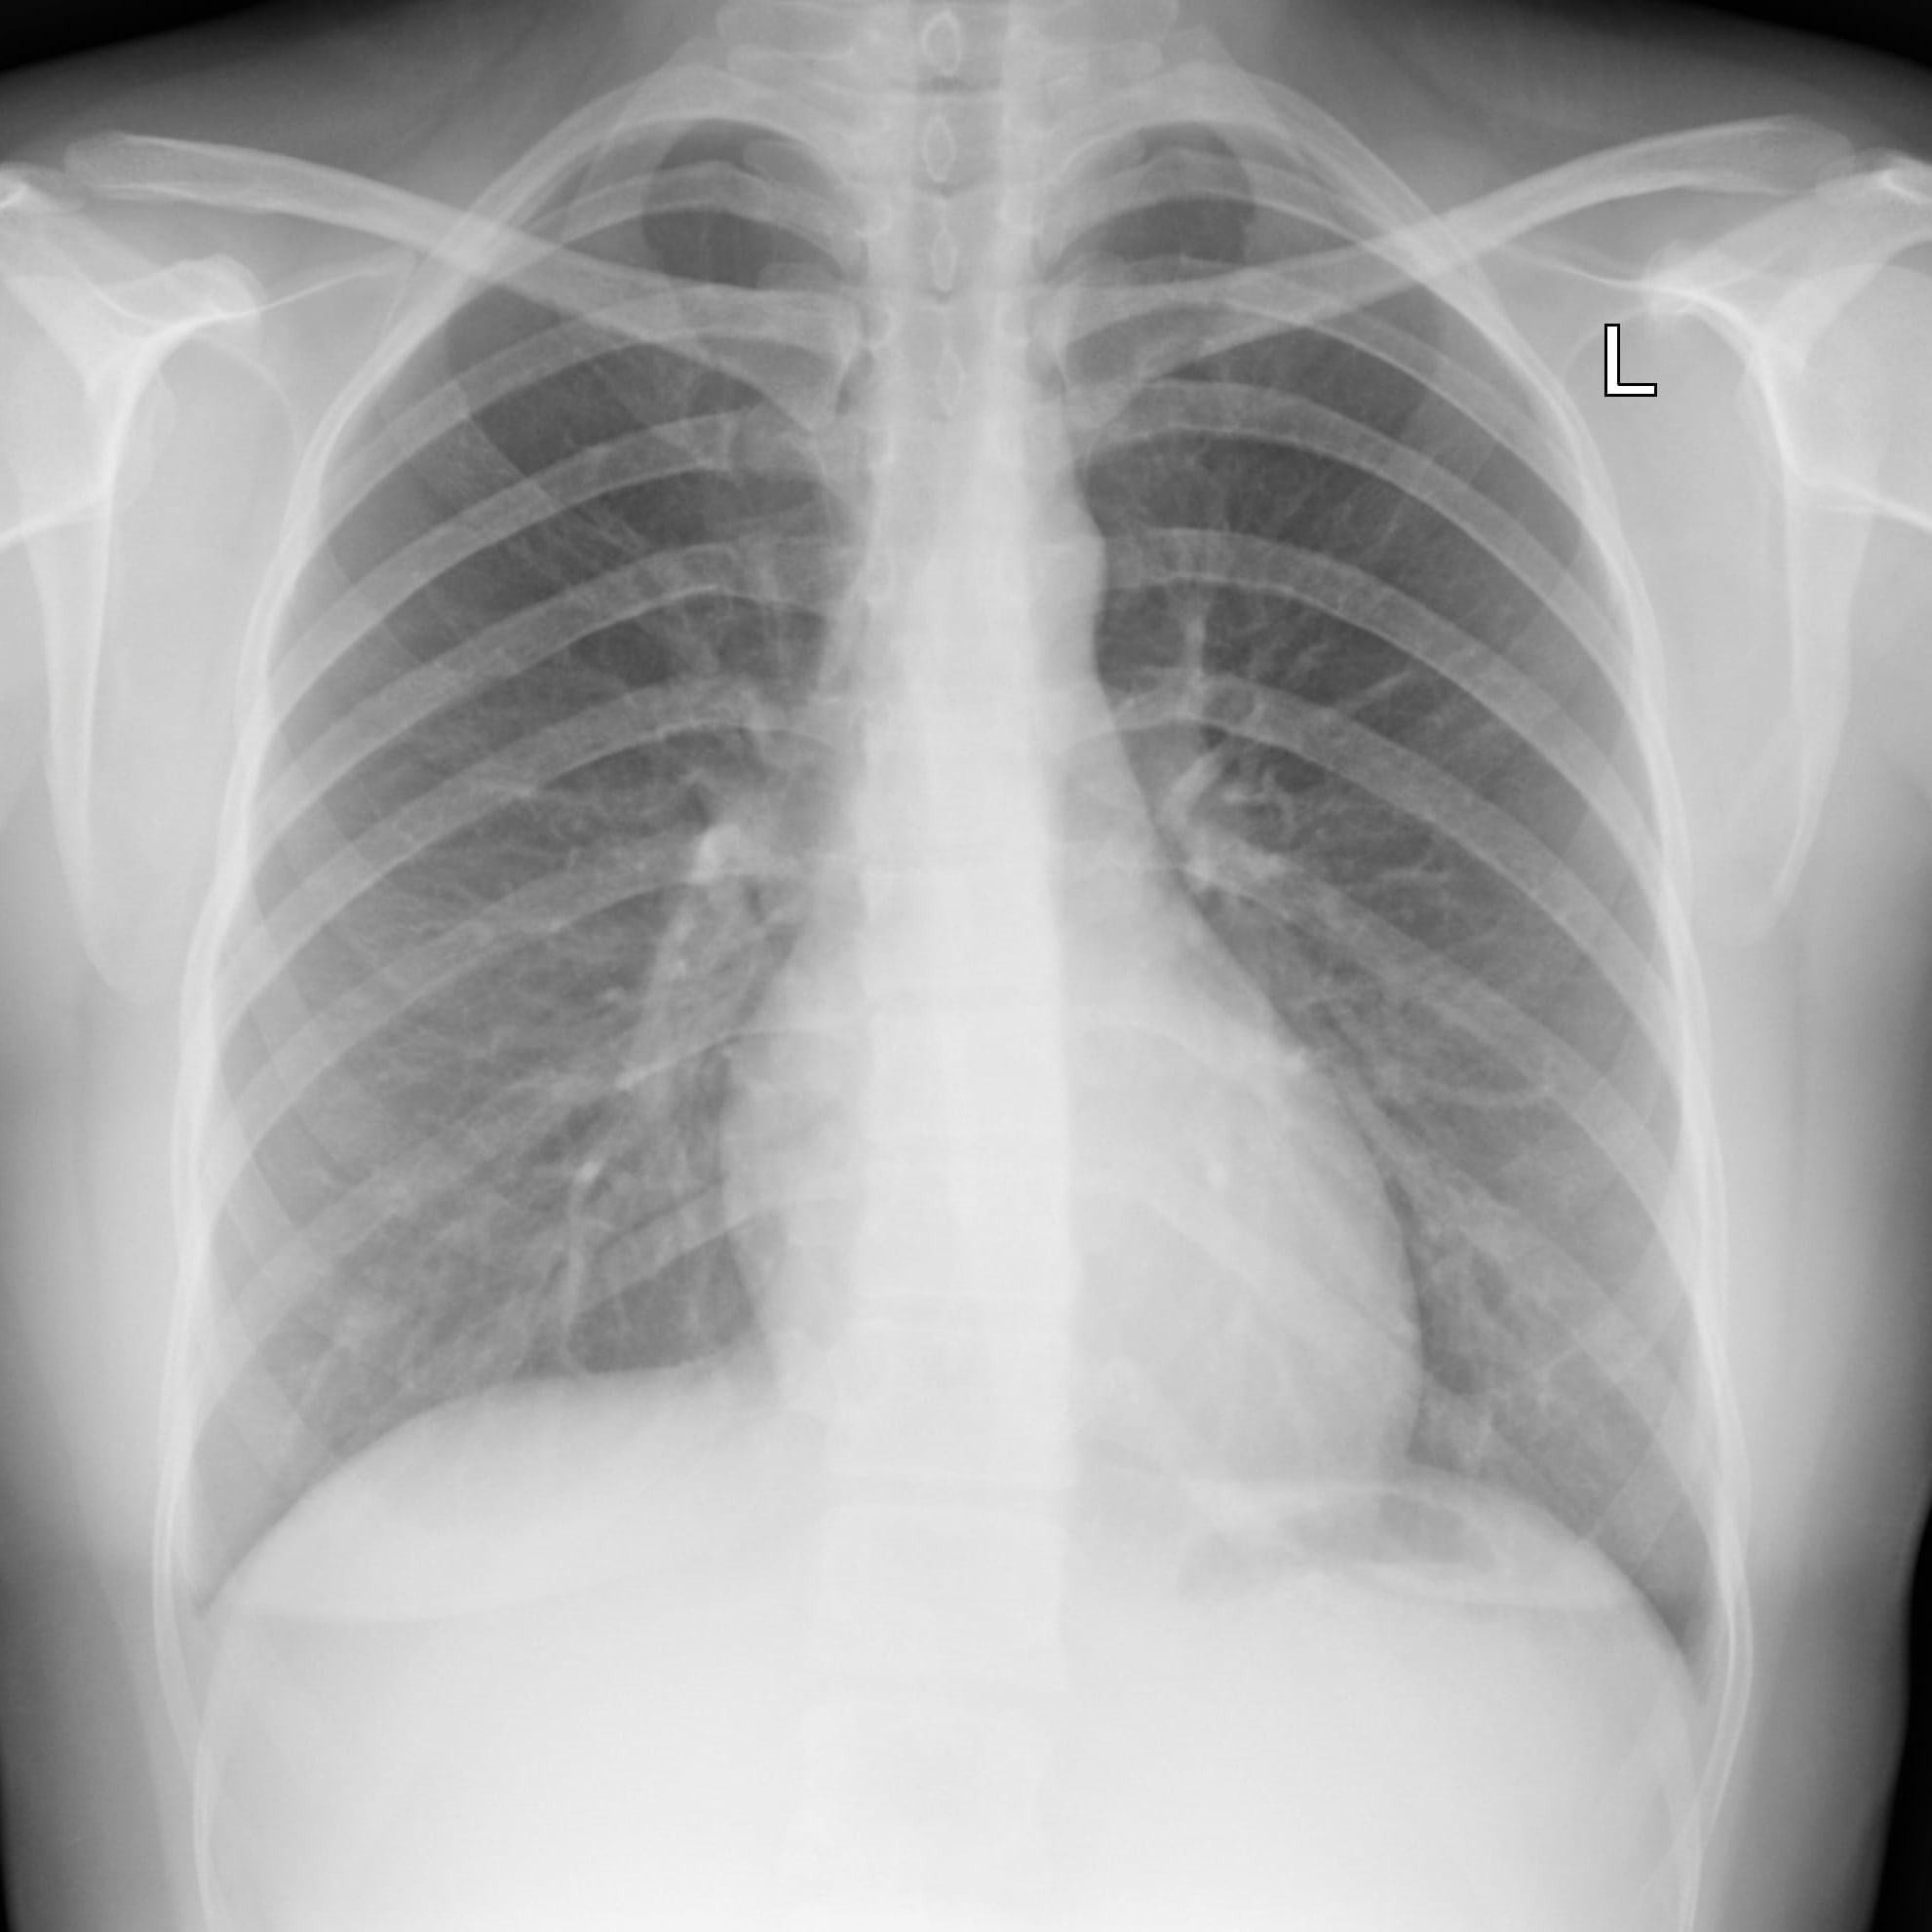

Every chest X-ray undergoes rigorous dual reading by NIOSH-certified B-Readers, adhering strictly to international ILO guidelines to ensure accuracy and consistency.

A chest X-ray is taken at a participating radiology clinic. The Lungscreen ID must be included in the image data.

All X-rays are read by accredited B-Readers using the ILO classification system. Each image is reported by at least two independent Radiologists.